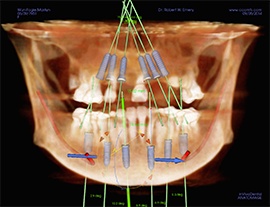

Computer-Guided Surgery

Computer-guided surgery, with the aid of modern and increasingly sophisticated software, enables the surgeon to plan the operation by means of a computer program, step by step, starting from a proper dental CT scan. It also allows very accurate transformation of this virtual surgery to a non-traumatic and micro-invasive real surgery.

After the 3-D CT scan of the dental area to be treated is completed, this scan will be imported into a highly technological software program that will elaborate two- and three-dimensional anatomical structures, enabling us to carry out a virtual computer simulation. We plan the implant placement and prosthetic structure precisely to a tenth of a millimeter. Other additional advantages of this method are the possibility of preventing surgical risk, the speed of this operation, and the rehabilitation period of the patient without the impact characteristics of traditional techniques.